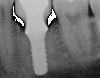

The entry of inflammatory cell infiltrate into the connective tissue (Figure 1 and Figure 2) differentiates peri-implantitis from peri-implant mucositis.1 Unlike a natural tooth—where periodontal fibers, transepithelial fibers, and gingival fibers absorb this exudate—none of these fibers are present around an implant (Figure 3). This allows the inflammatory cell exudate to directly enter the bone, resulting in bone loss and concomitant soft-tissue loss (Figure 4).1

Fig 3. Unlike a natural tooth, an implant does not have periodontal fibers, transepithelial fibers, or gingival fibers to absorb the exudate around it.

Figure 3